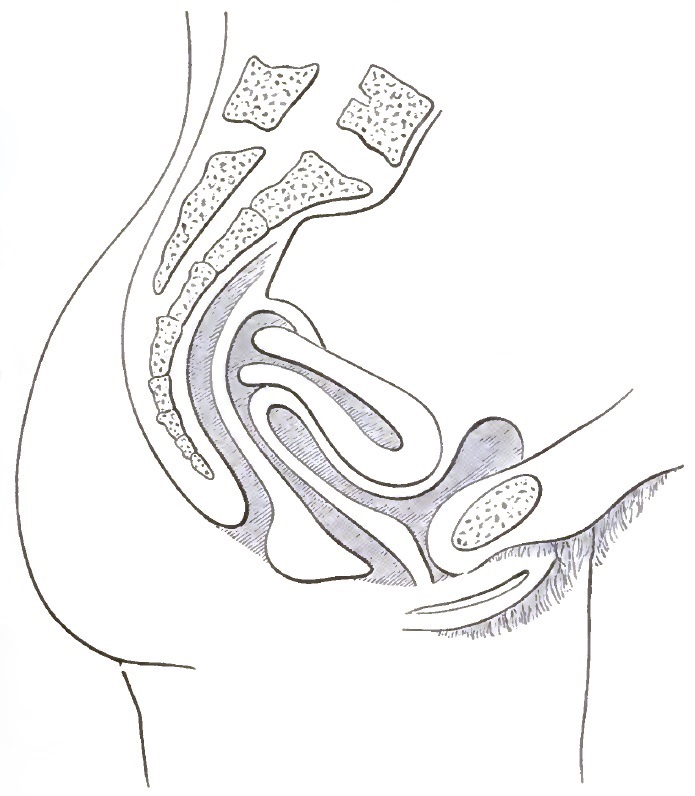

| 1. | THE CLASSICAL REPRESENTATION OF THE PELVIC ORGANS |

| 2. | THE CORRECT REPRESENTATION OF THE PELVIC ORGANS |